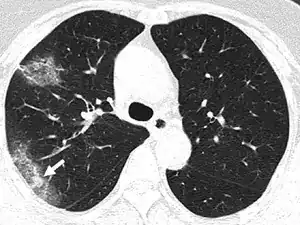

Silent hypoxia (also happy hypoxia)[1][2] is hypoxia that does not coincide with shortness of breath.[3][4][5] It is known to be a complication of COVID-19.[6][7] It is speculated that this condition is caused by SARS-CoV-2 affecting the blood flow of the lungs' airways, in addition to the blood vessels within the lungs, which must match in order to allow proper airflow, but not affecting them enough to cause shortness of breath.[8][9] It is also speculated that silent hypoxia may be caused by the formation of small blood clots within the lungs.[10][11][12] It has been shown that the breathing rates of patients with COVID-19 gradually increase, which in turn leads to silent hypoxia.[13] It has also been shown that COVID-19 patients experience lesser levels of shortness of breath after exercise than non-COVID-19 patients.[14] The condition is also known to be caused by walking pneumonia[15] and altitude sickness.[16][17][18]